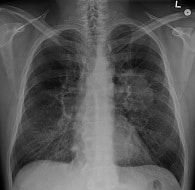

Au démarrage du projet en août 2013, le crizotinib est une thérapie ciblée d’administration orale autorisée seulement pour le traitement des patients qui souffrent d’un cancer bronchique non à petites cellules (CBNPC)3 présentant une altération moléculaire spécifique (translocation de ALK) dans leur tumeur. Cependant, le crizotinib agit sur trois cibles moléculaires ALK, MET et ROS1 qui sont retrouvées dans plus d’une quinzaine d’autres cancers. L’étude s’est terminée en février 2018. Elle a inclus 246 patients, âgés de 1 à 92 ans, dont la tumeur présentait une des cibles du crizotinib (plus de 20 types histologiques différents). Trois cohortes étaient dédiées au CBNPC, spécifiques aux amplifications de MET (25 patients), aux mutations de MET (29 patients) et aux translocations de ROS1 (39 patients).

Les résultats centrés sur les patients avec un CBNPC et présentés le 25 septembre 2018 à la WCLC par le Pr Denis Moro-Sibilot, oncologue thoracique au CHU de Grenoble, et expert pathologie des cohortes poumons, montrent que le crizotinib apporte un bénéfice dans chacune des altérations MET et ROS1, avec toutefois une ampleur différente. L’activité du crizotinib en présence d’une translocation de ROS1 est très significative et en cohérence avec les données qui ont conduit en 2016 à une extension d’AMM pour cette cible. Les résultats dans les mutations de MET, notamment sur l’exon 14, vont conduire à une nouvelle extension d’indication. L’activité plus modeste sur les amplifications de MET apporte des données utiles à la communauté dans l’exercice de la médecine de précision.

Ce sont les résultats de la cohorte dédiée aux CBNPC mutés BRAF V600 (101 patients), à présent fermée, et de la série des CBNPC mutés BRAF non V600 (17 patients), qui sont présentés le 25 septembre 2018 à la WCLC, par le Pr Julien Mazières, pneumologue au CHU de Toulouse, et expert pathologie de la cohorte poumon. Le vemurafenib confirme une activité intéressante (45 % de taux de réponse) chez des patients prétraités mutés V600, positionnant les inhibiteurs de BRAF en monothérapie comme une option chez les patients pour qui la bithérapie anti-BRAF et anti-MEK n’est pas disponible.